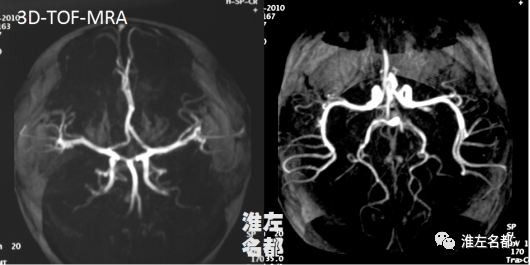

2010-9-13 MRI

△颅脑3D-TOF-MRA:所见颅内动脉未见异常。

3、此患儿,起病前有明确头部跌伤史,典型的偏瘫症状,影像学证实右侧豆纹动脉区梗死,诊断外伤性脑梗死是没有问题的。文献报道,大多数儿童外伤后基底节-内囊梗死的血管影像学显示的同侧颈动脉和大脑中动脉无异常,本病例亦是如此。

4、儿童颅脑外伤后出现脑卒中症状,急诊CT有助于明确是否颅内出血,但对较小的早期脑梗死可能不敏感,24小时或数天后才可显示基底节梗死低密度;MRI则可在发病数小时内显示急性脑梗死病灶,但小儿对MRI检查配合度低,需要镇静。脑血管成像有助于明确是否合并动脉夹层或烟雾病等血管病变;TOF-MRA因不需要注射对比剂,在小儿较CTA有优势。